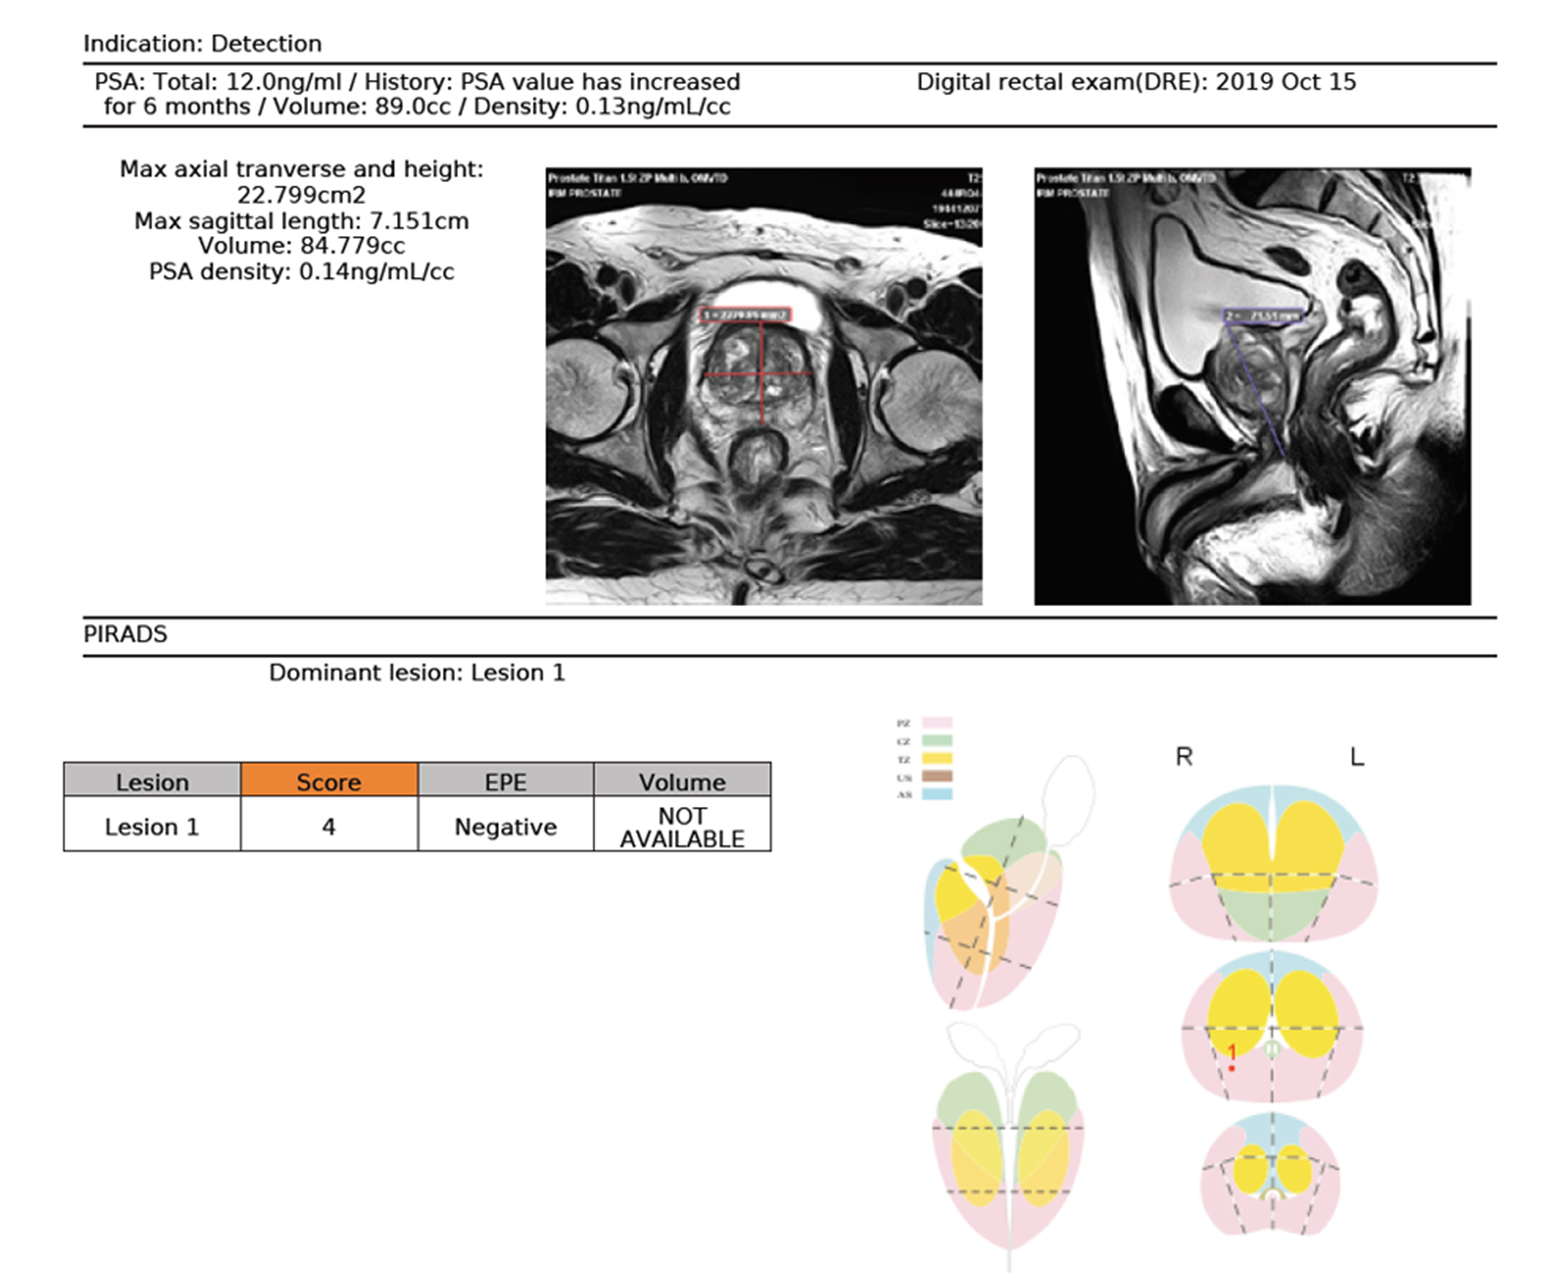

Онкология тела

Оптимизированные решения для комплексной визуализации при патологиях груди и простаты

- Обнаружение, классификация и характеристика опухолей с быстрым доступом к качественной и количественной информации

- Интегрированные и управляемые отчеты Pi-Rad и Bi-Rads для повышения эффективности

- Автоматический расчет кинетического распределения

- Количественная оценка микроперфузии и электронных значений b методом IVIM

- Инструменты расширенного анализа и сегментации

Расчет АЦП и других качественных и количественных карт

Многопараметрический просмотр и инструменты анализа для быстрой характеристики поражения

Интегрированная и управляемая отчетность Pi-Rads Bi-Rads